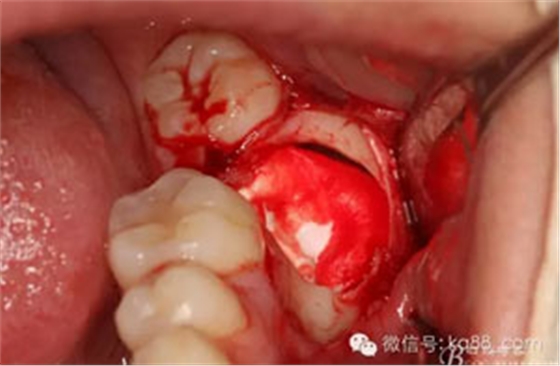

圖14.分開近遠中牙冠及牙根及周圍囊壁。

14.jpg